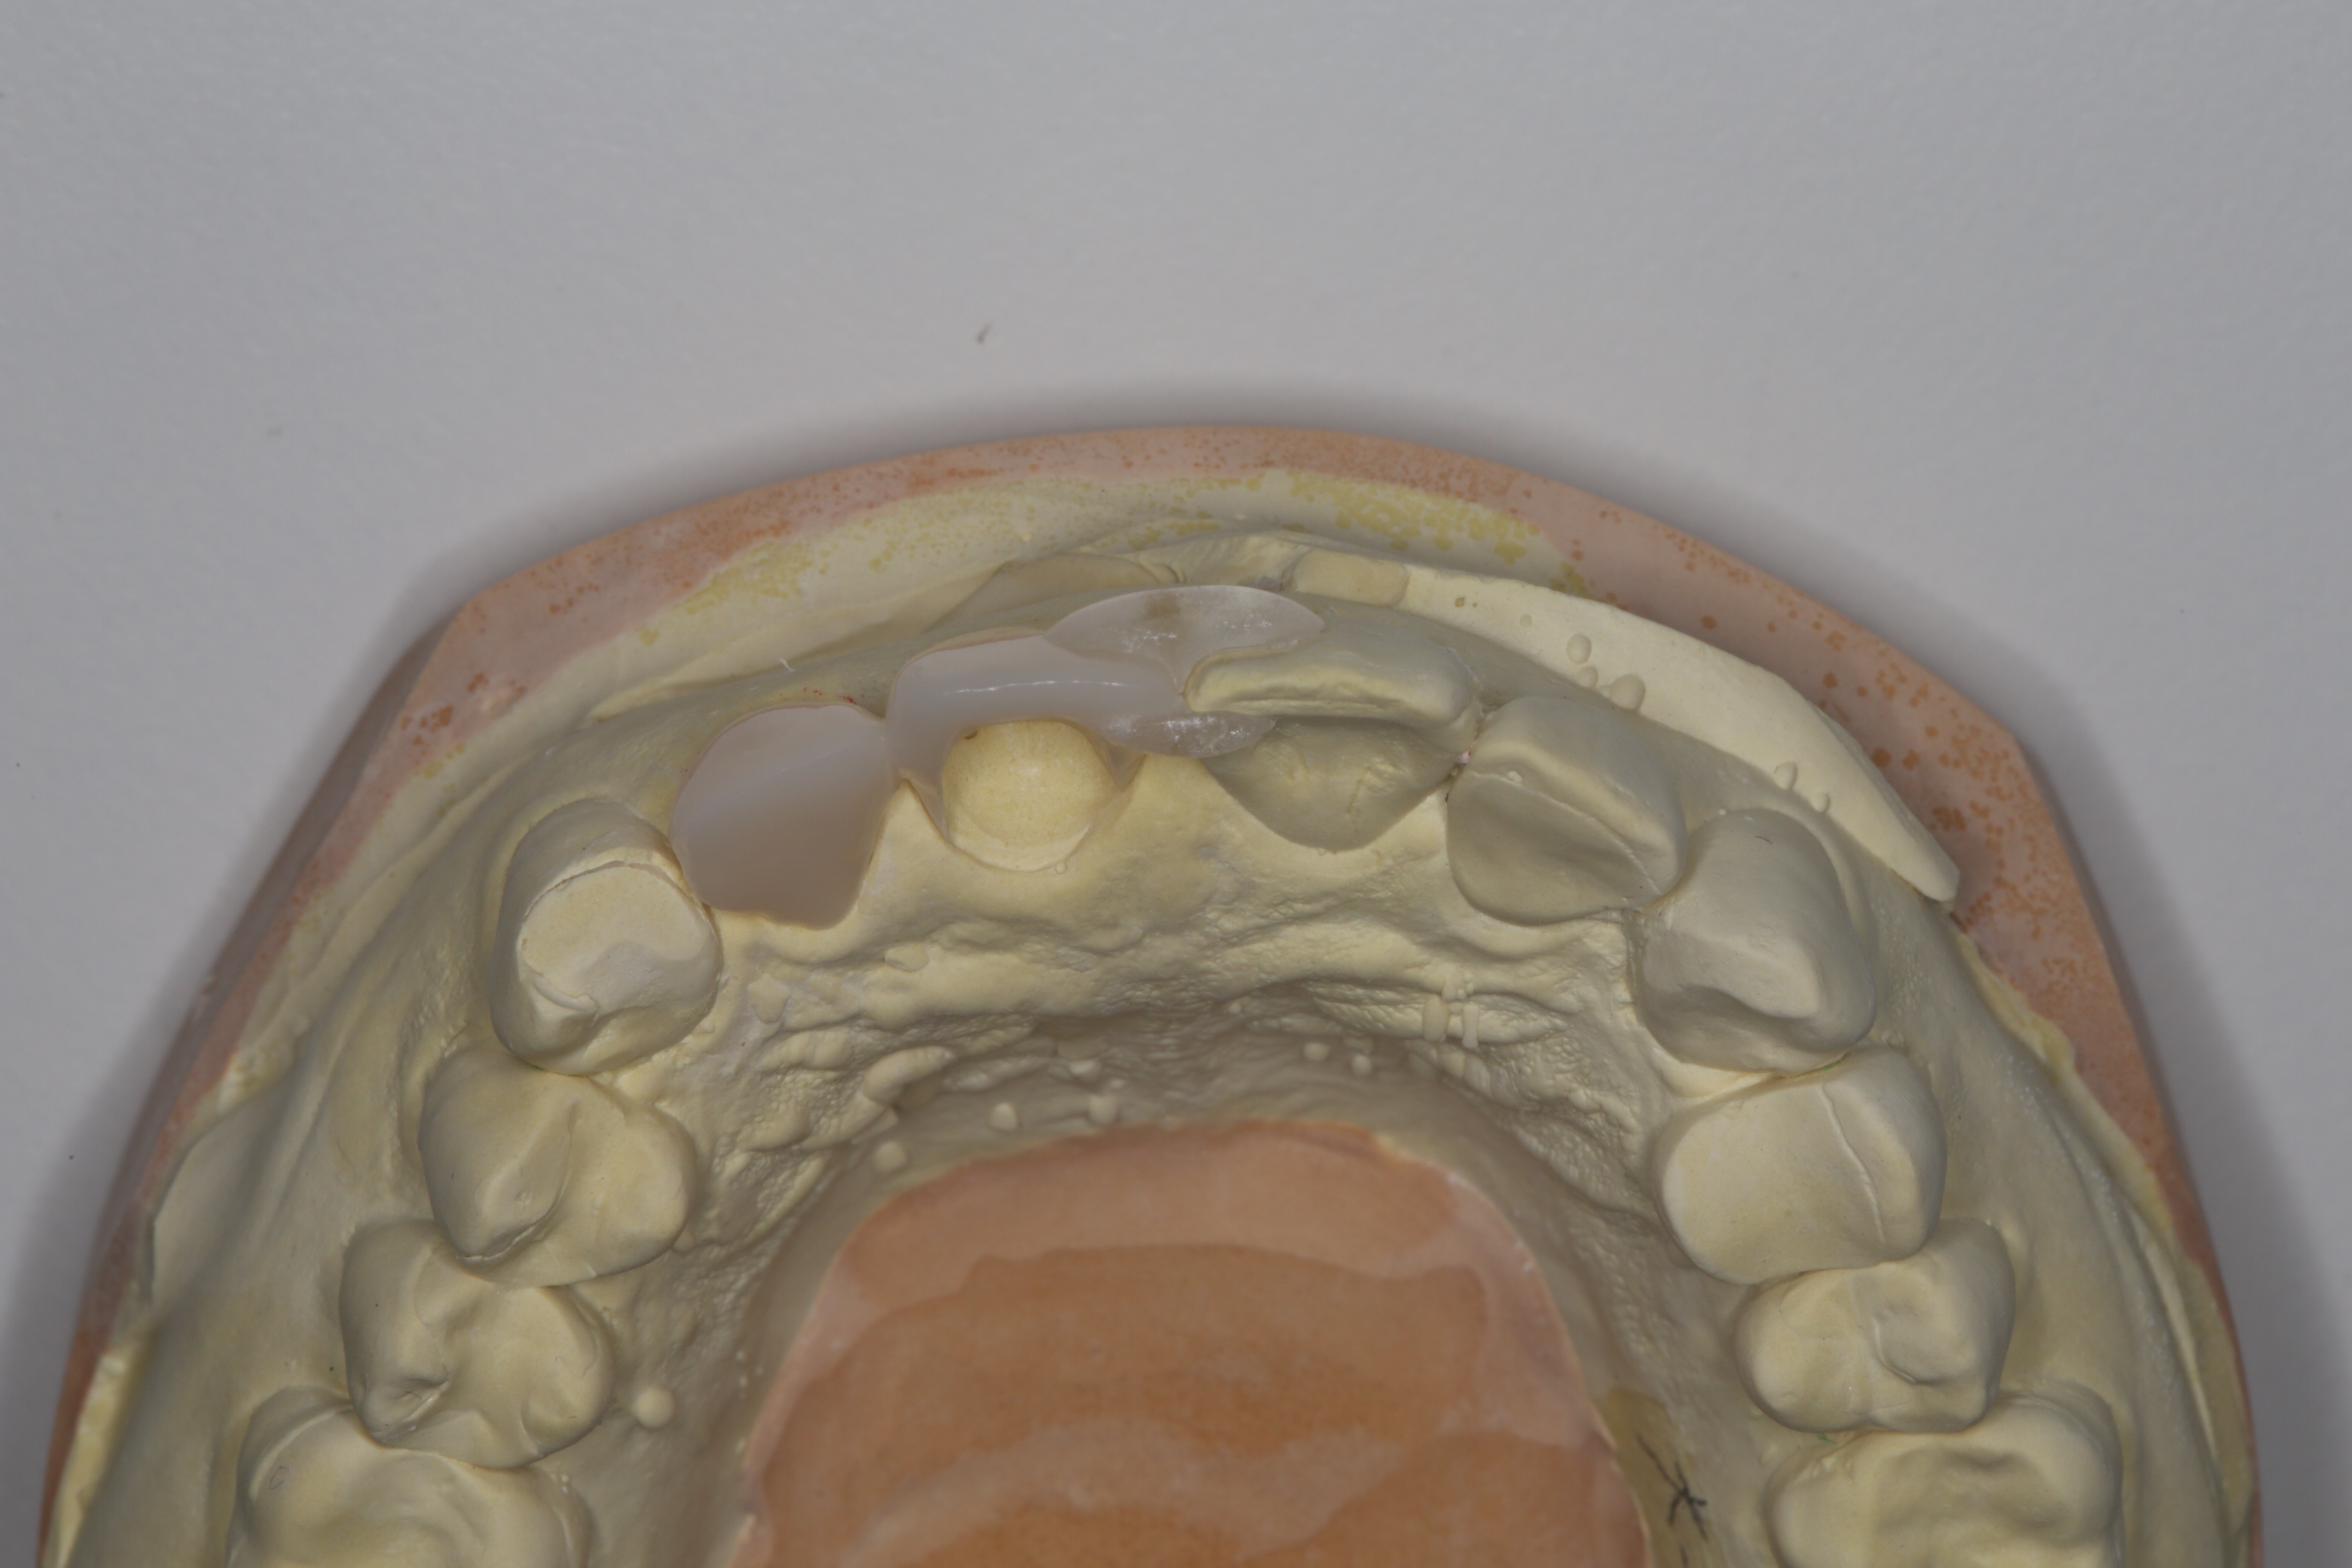

模型上でアナログサージカルガイドを製作し、オペに臨みました。

インプラントが骨と結合し、型取りを行いました。

実際の型取りから、歯の製作まで2ヶ月弱をかけました。